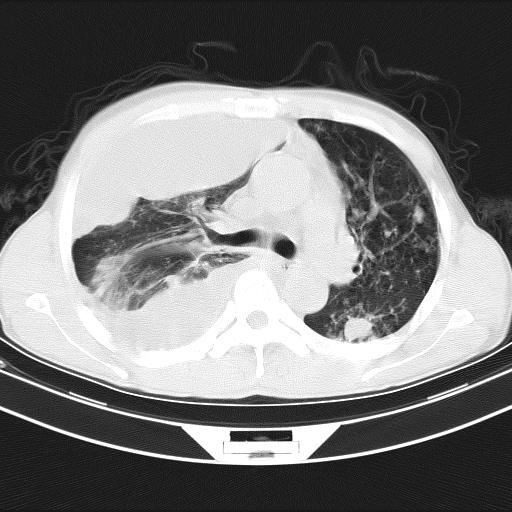

男性,44岁,结核病史多年。现胸闷气短,咳嗽,偶咳血。

1、右侧大量胸腔积液伴右肺压缩性膨胀不全,建议抽液治疗后复查 2、两肺继发性tb伴空洞形成。

1)两肺继发性肺结核伴空洞形成,左肺多发性结核球。2)右侧大量胸腔积液伴右肺部分膨胀不全。3)纵隔淋巴结肿大。

1,双肺多发结节 并空洞影改变, 左侧胸腔积液并部分包裹, 结合原病史首先考虑结核. 但也不除外其它.

2,左侧有一根肋骨陈旧性骨折? 建议追查 .